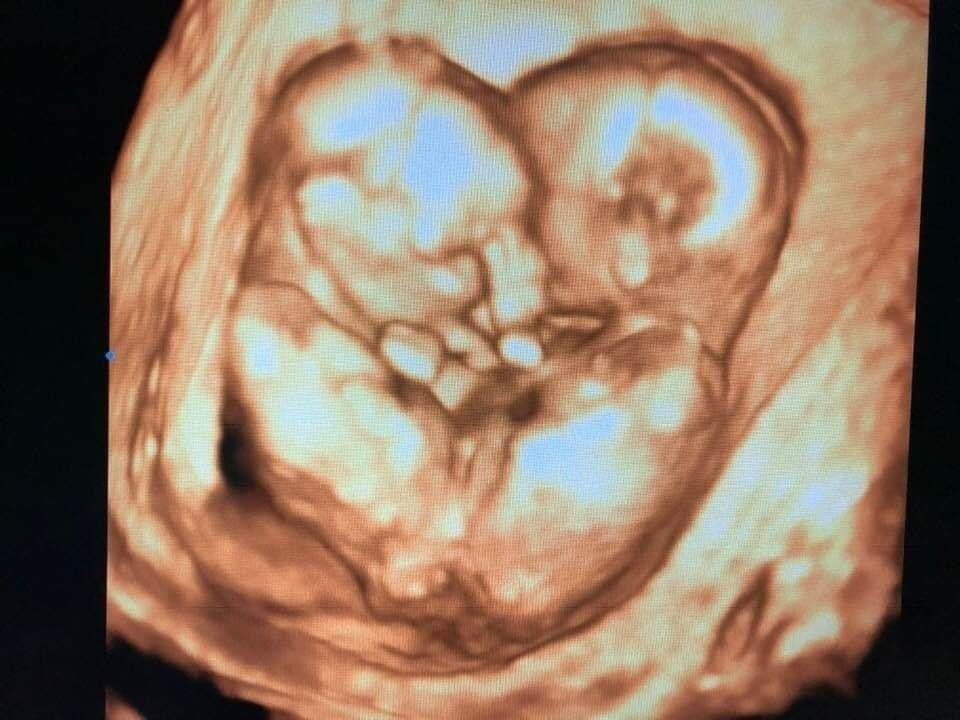

| Hình ảnh siêu âm phát hiện Trúc Nhi - Diệu Nhi dính vùng bụng chậu được thạc sĩ, bác sĩ Nguyễn Đình Vũ lưu lại |